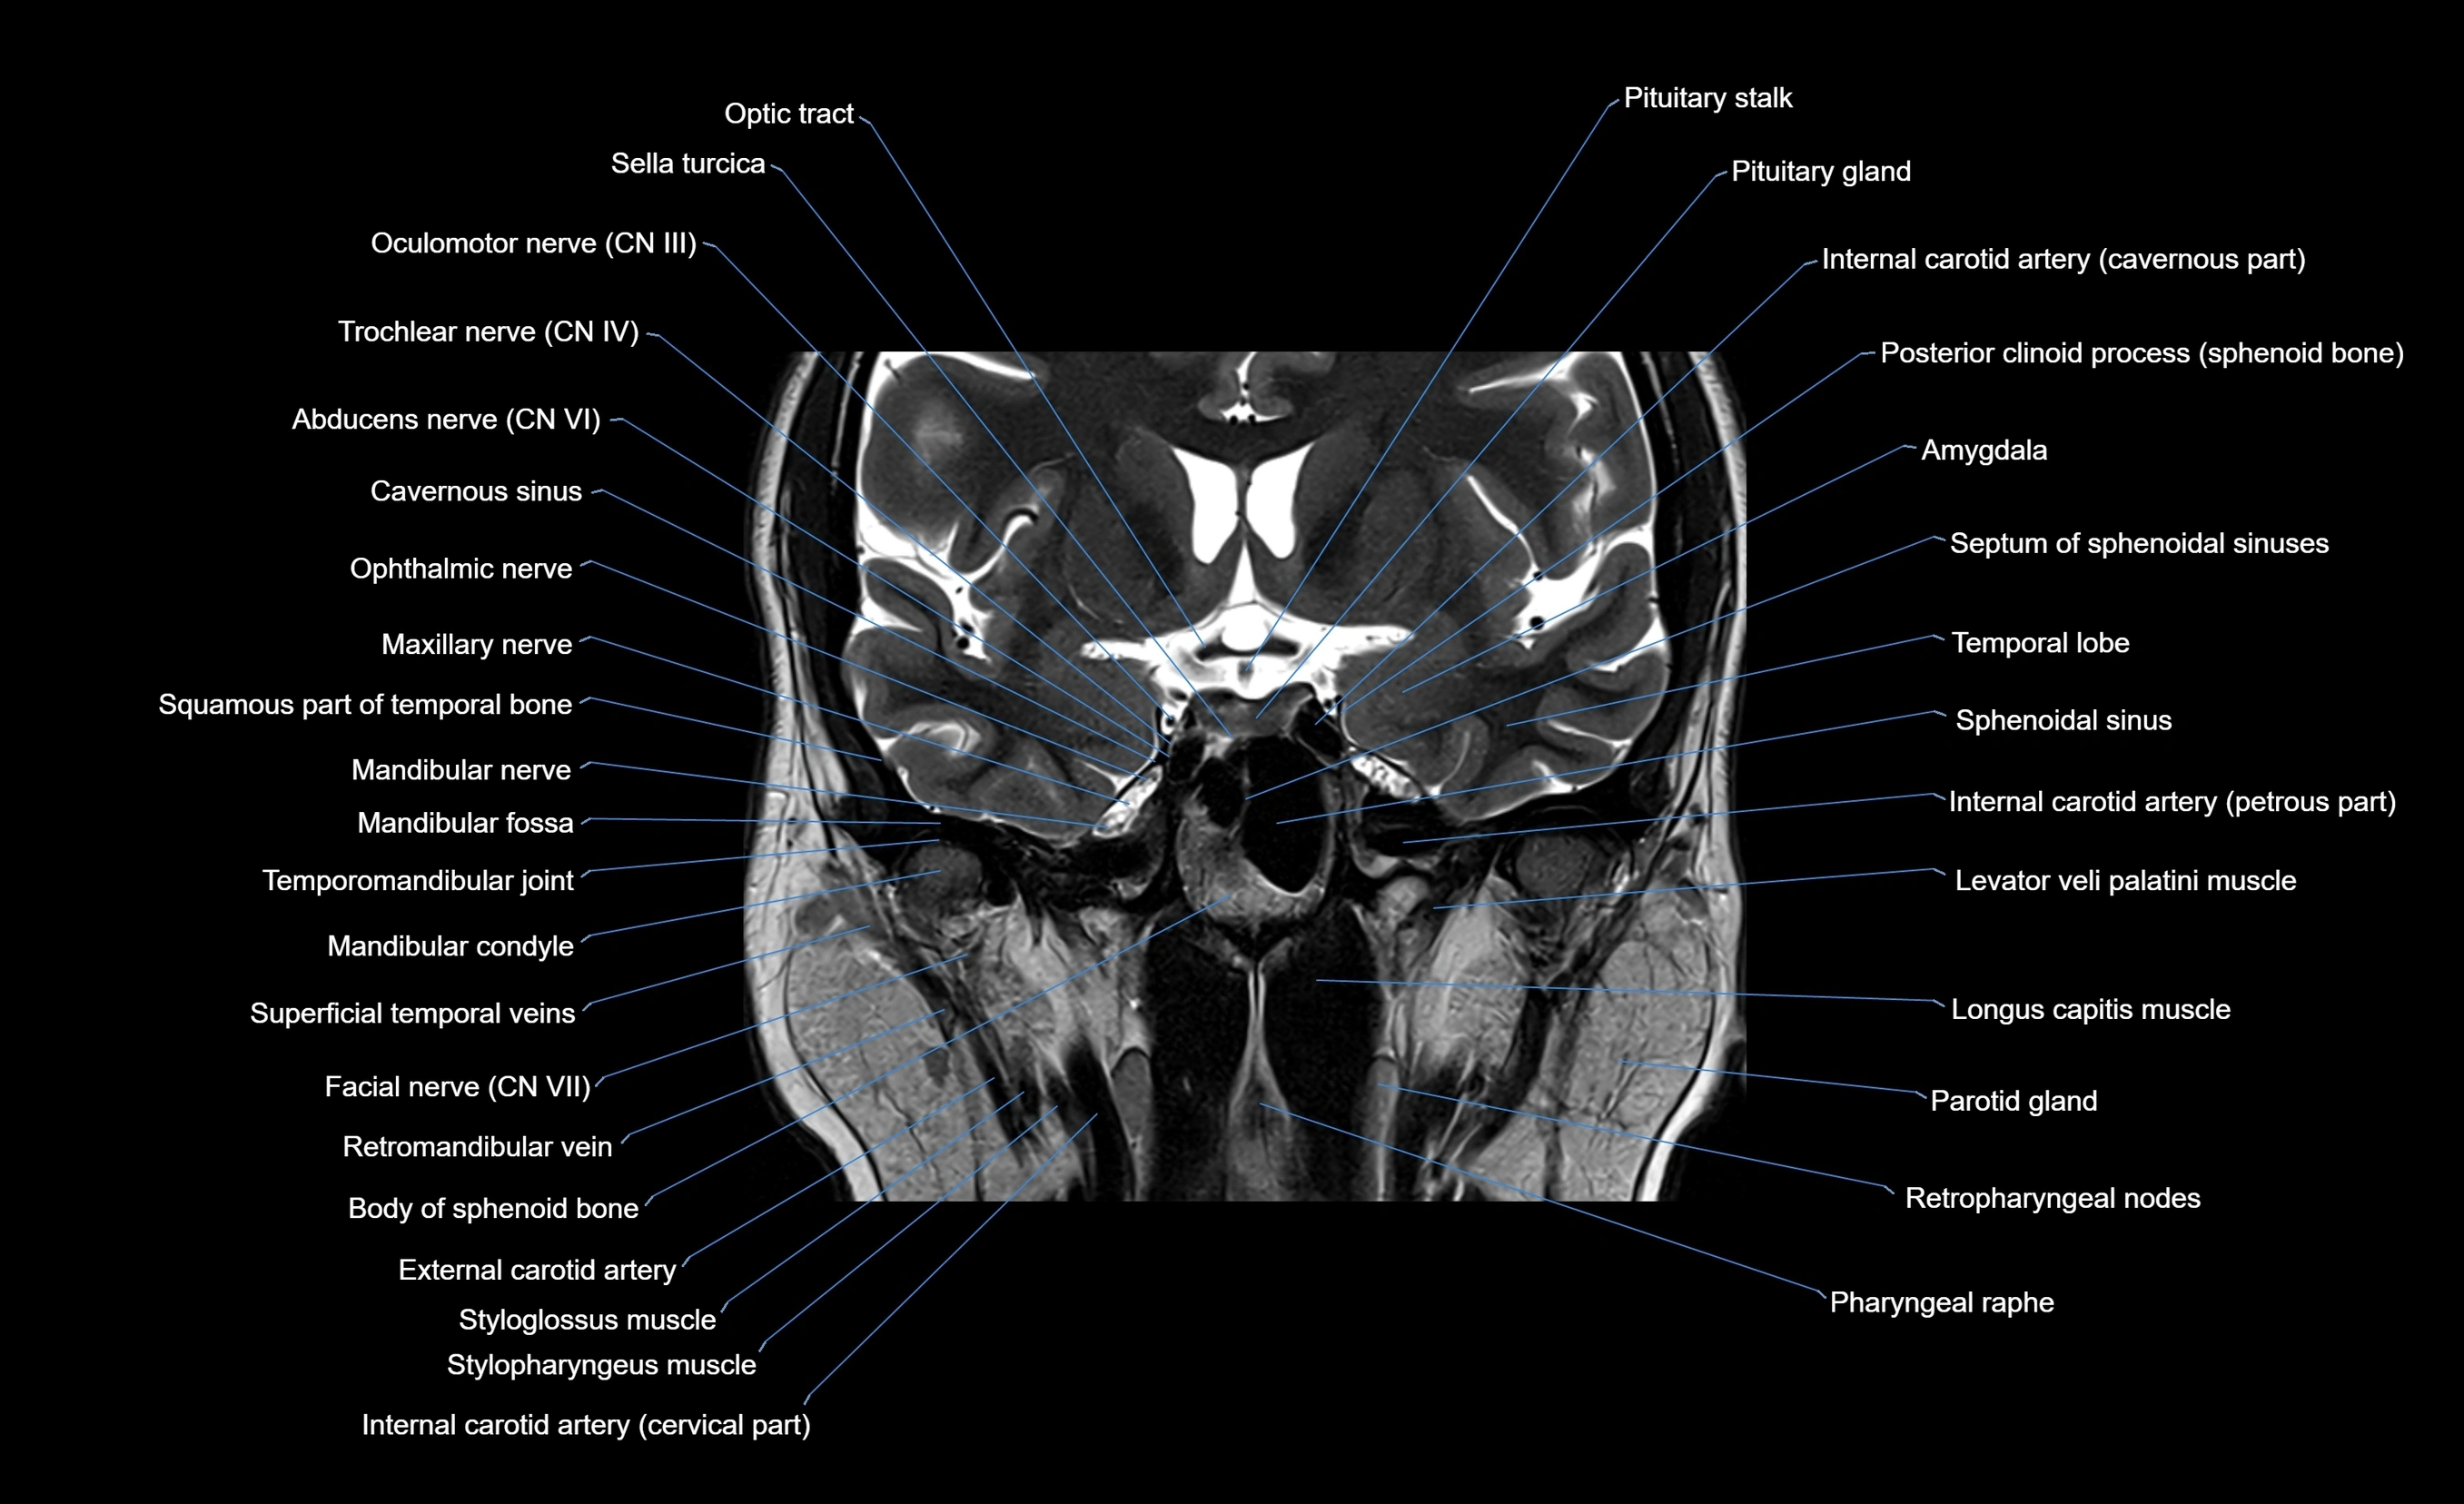

MRI images